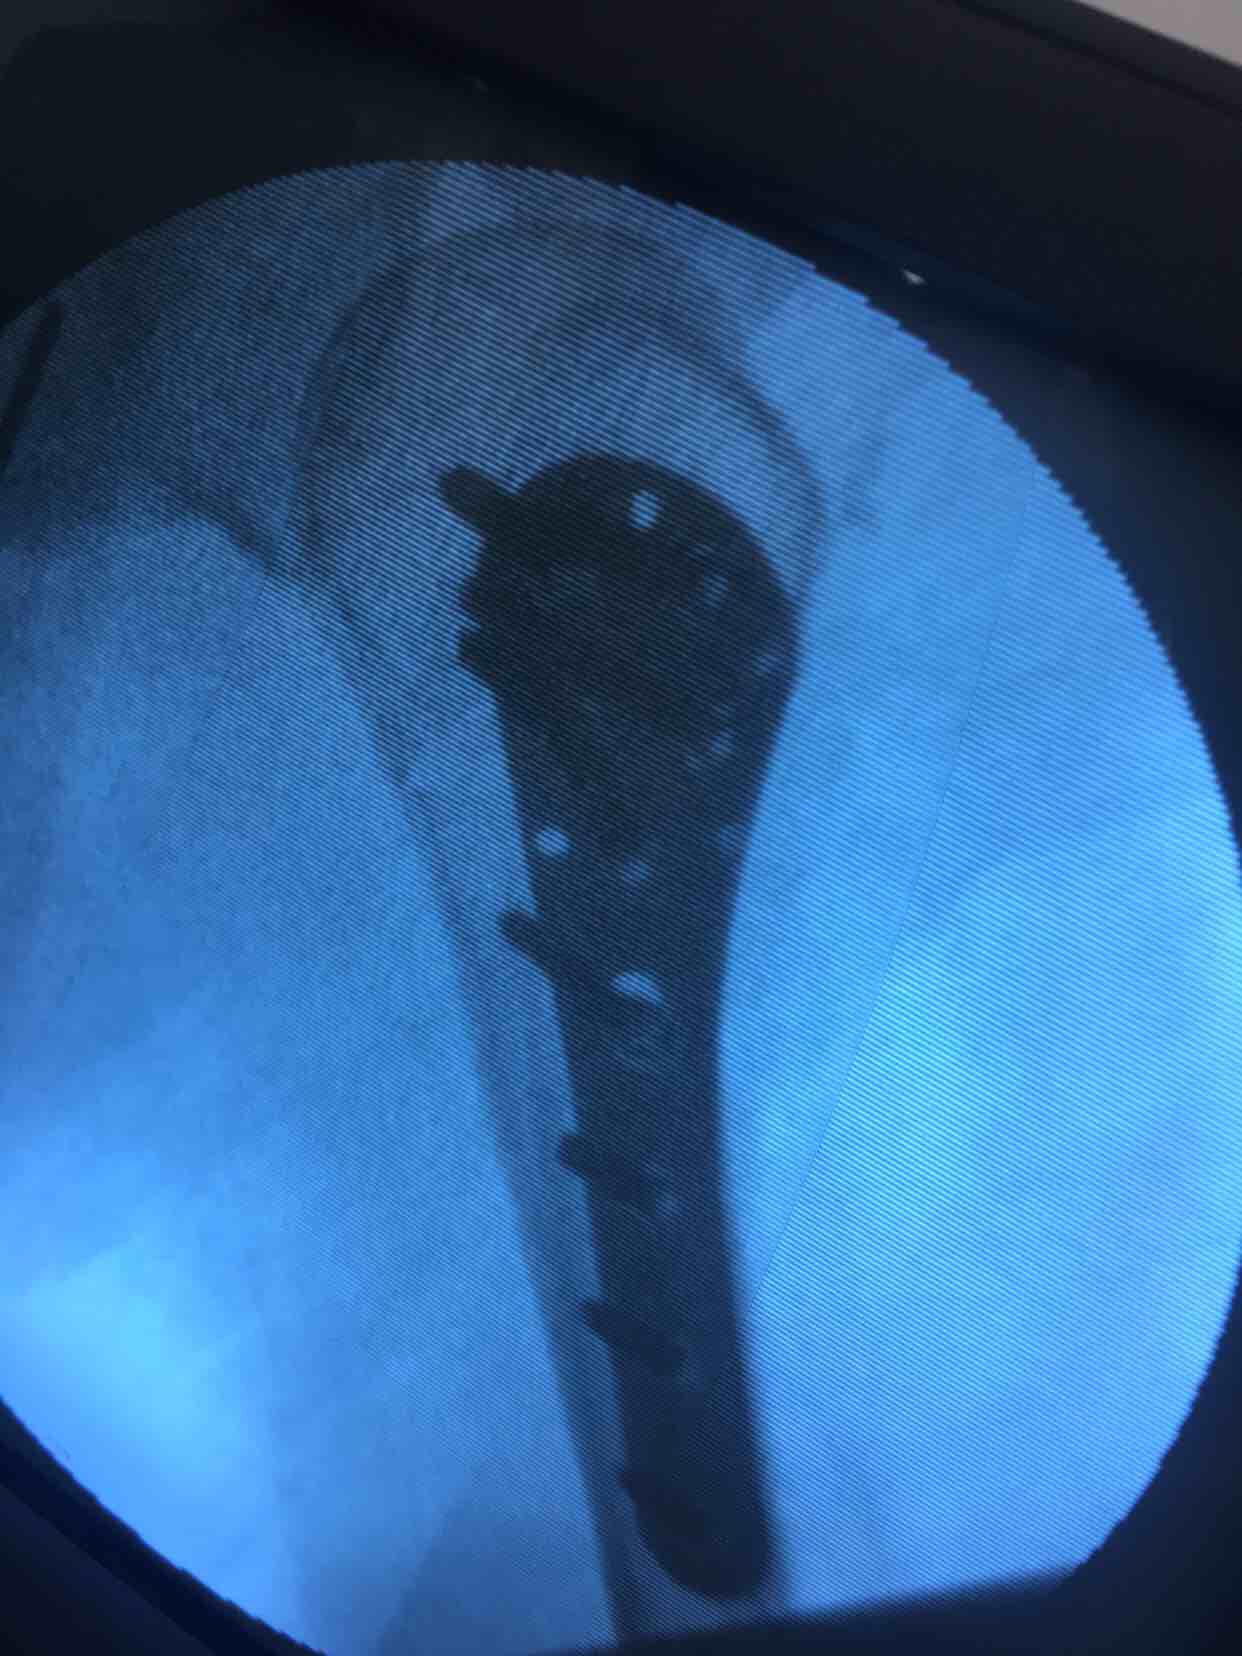

诊断:肱骨外科颈粉碎性骨折(右)完善术前准备,在臂丛麻醉下行切复内固定术,选肱骨近端锁定钛板,保持稳定性及早期功能锻炼。术后抗炎,消肿等处理。

手术最大优势尽可能解剖复位,保障骨折稳定,早期功能锻炼,避免肩肘腕综合征,骨折移位风险发生。